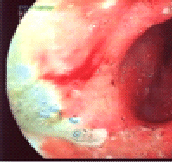

Эта неприметная бактерия является виновником развития у человека хронического антрального гастрита (изменение слизистой оболочки по типу "булыжной мостовой"),

хронического эрозивного гастродуоденита,

язвенной болезни желудка и двенадцатиперстной кишки, и что самое опасное, присутствие в организме хеликобактерной инфекции может являться причиной возникновения рака желудка, причем происходит это вне зависимости от возраста пациента!